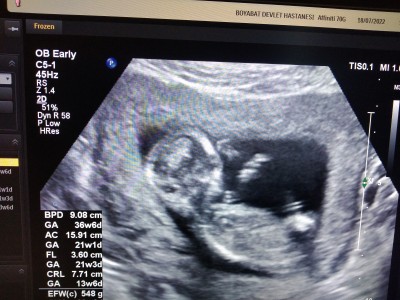

Kemik yapısından cinsiyet tahmini yapabileniniz var mı kızlar sizce erkek mi kız mı 14haftalıktı ultrason da doktor devlet hastanesi olduğu için 17den önce söyleyemem dedi

Kız bence oyle tahmin  ediyoeum kafa yapısından

Bence kız,erkek olsa kafası biraz daha uzun oluyor ince uzun